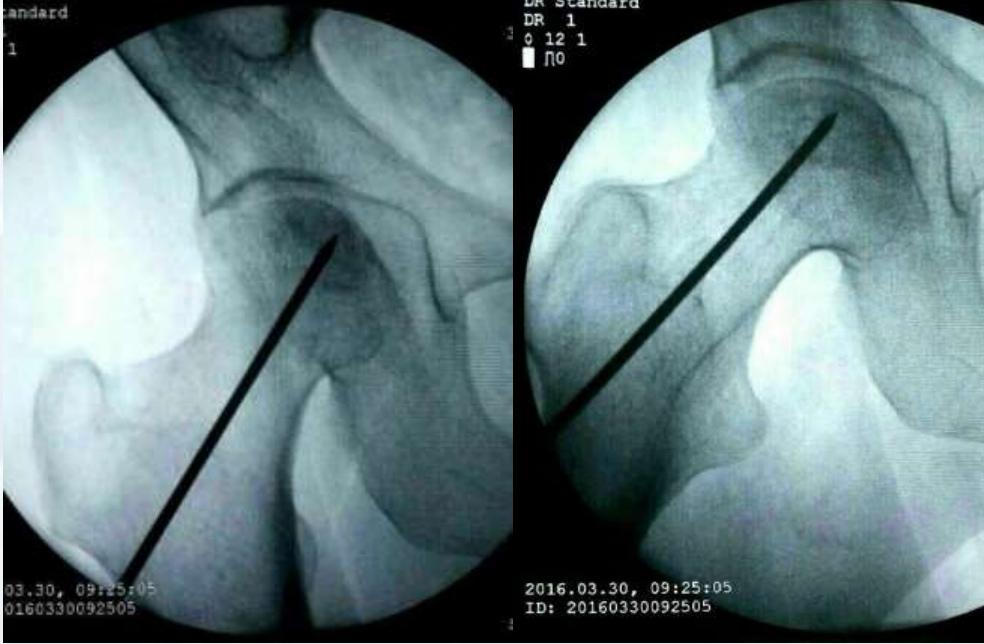

手术方法1:髓芯减压

为最常用的保髋手术方式,可同时配合自体松质骨、自体骨髓间充质干细胞、 BMP、富血小板血浆( PRP )等一起植入。

手术方法2:钽棒支撑